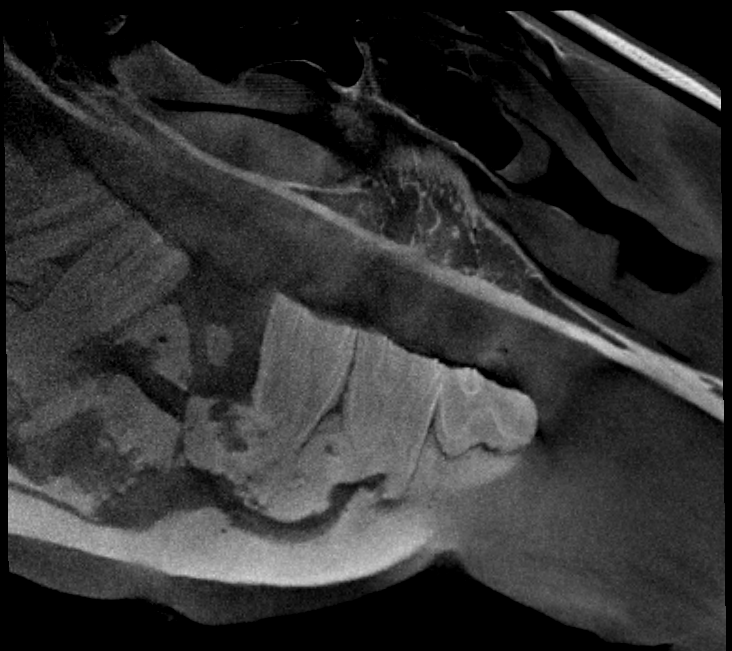

Our High Definition Volumetric Imaging (HDVI) technology represents the most advanced stage of Flat Panel CT technology. It offers exceptional diagnostic imaging for both hard and soft tissues, in diagnostic settings and intraoperative theaters. It is the gold standard for orthopedic applications.

Scan of the head, neck and limbs in standing position

Scan of the standing horse

Pegaso scans head, neck and limbs of the standing horse